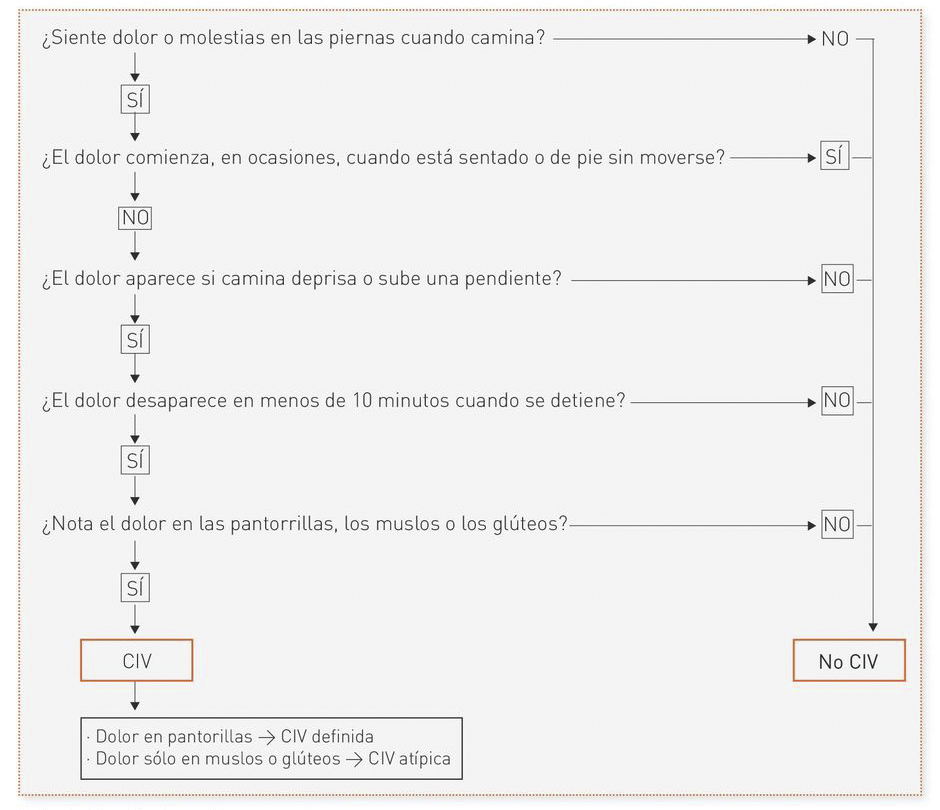

En pacientes con insuficiencia arterial existen dos tipos característicos de dolor:5

- La claudicación intermitente. Una molestia o incapacidad asociada al ejercicio, la mas común es como un dolor tipo “calambre” en la pantorrilla , y que el reposo ayuda a aliviar rápidamente.

- El dolor isquémico en reposo. Suele aparecer como un dolor nocturno, insoportable para el paciente mas frecuente en la zona de los pies o cerca de una úlcera isquémica o dedo gangrenoso.

- Medical Dosplus.Enfermedad arterial periférica. Dr José M. Romero.[monografía en Internet].2010.[acceso 28 de enero 2020]. Disponible en file:///C:/Users/USUARIO/Desktop/BLOG%20CMUC/Enfermedad_arterial_periferica.pdf